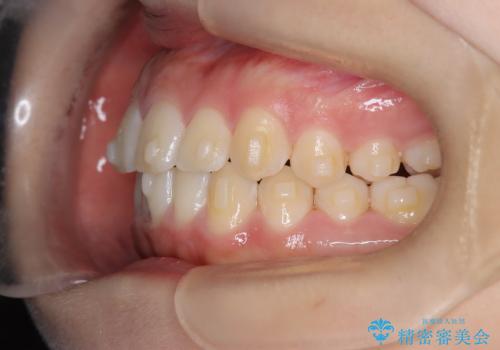

- 患者様は、**下の前歯のがたつき(叢生)**を気にされて来院されました。

下の前歯のがたつきは解消され、滑らかなアーチ状の歯並びとなりました。